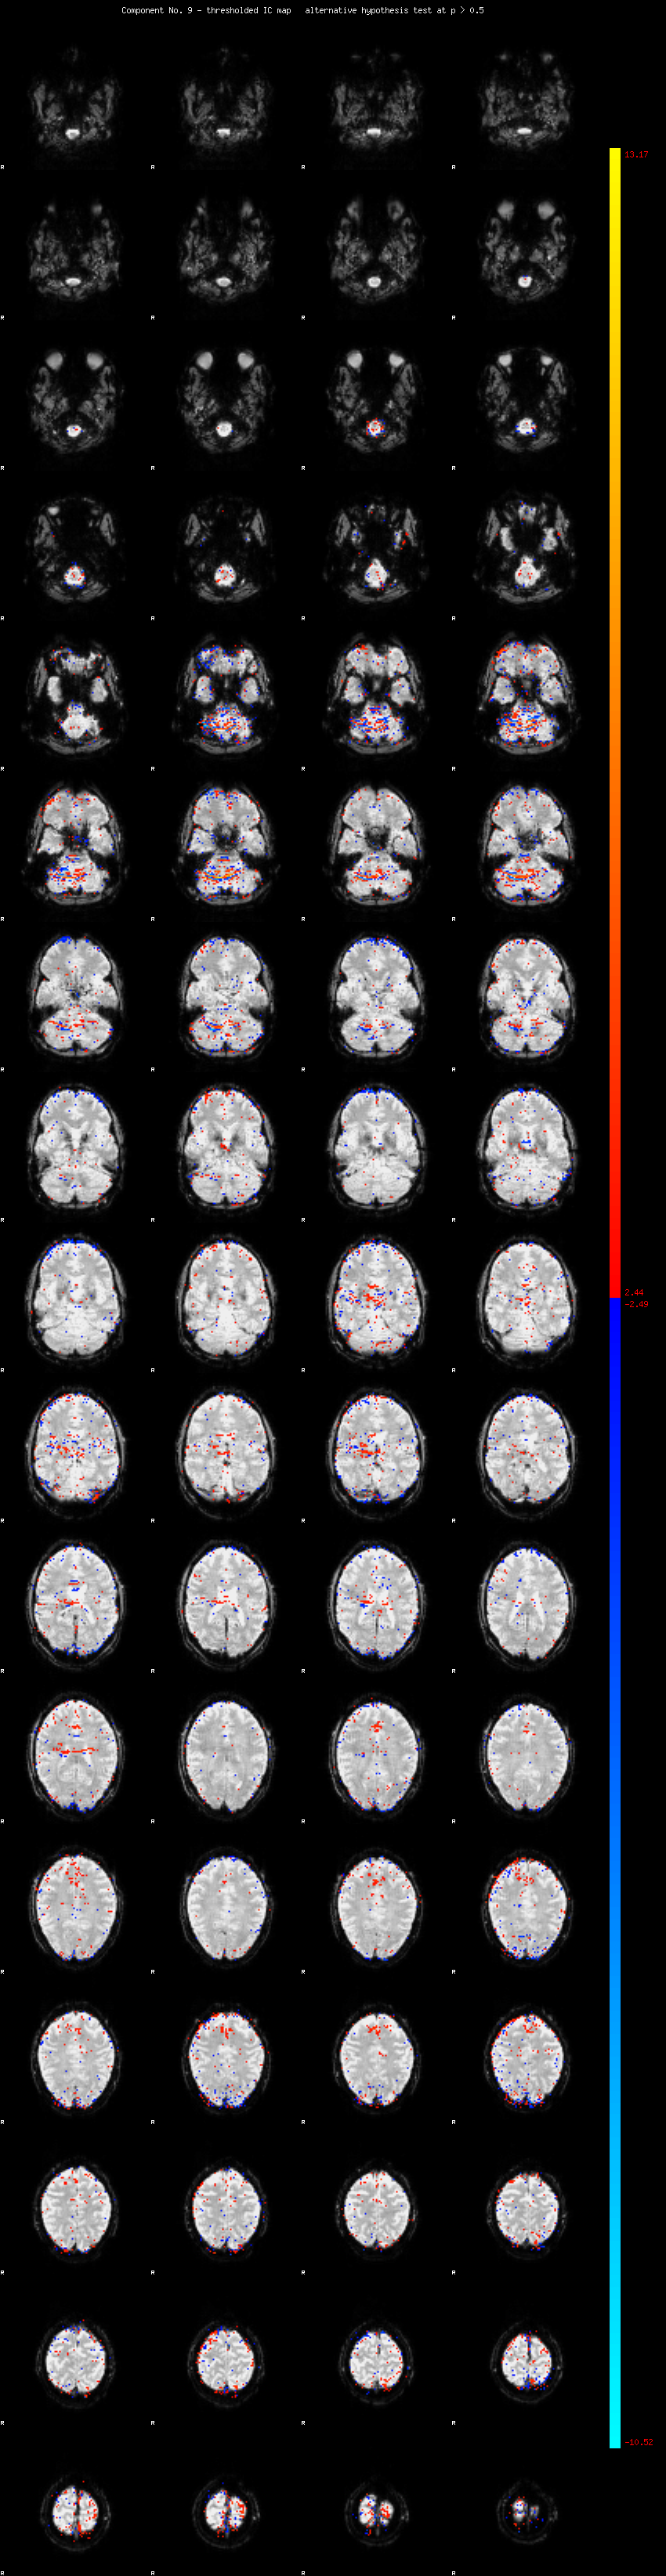

MELODIC Component 9

2.17 % of explained variance;     1.44 % of total variance

MMfit